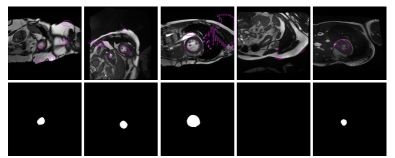

Generating partially labeled images  The training exams are divided into a small set of fully labeled images, 𝒟ssubscript𝒟𝑠\mathcal{D}_{s}, and a larger set of images with reduced supervision, 𝒟wsubscript𝒟𝑤\mathcal{D}_{w}, where only a handful of pixels are labeled. Concretely, we employ the same partial labels as in [24, 25], which are obtained by eroding iteratively the full pixel-wise masks with a kernel of size 10 ×\times 10, until the smallest possible contour is obtained. To evaluate how increasing the amount of both fully and partially labeled affects the performance, we evaluated the proposed models in three settings, referred to as Set-3, Set-5, and Set-10. In these settings, the number of fully labeled images is 3, 5 and 10, respectively, while the number of images with partial labels is ×\times5 times the number of labeled images.

Several failure cases from proposals are depicted in Fig 4. With this strategy, these errors are propagated during training, which might explain the low performance compared to our method. In addition to lower performances, this approach requires to fully train a first model, generate pseudo-labels and then re-train a second model with the generated masks. This contrasts to our method, which is trained in an end-to-end manner.

Refer to caption

Figure 4: Failure cases which are employed as pseudo-labels in the proposals-based approach (top), whose errors are reinforced during training, and their corresponding ground truth. Best viewed in colours.